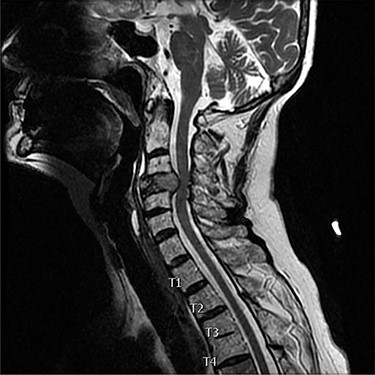

A 73-year-old female presented with neck pain and shooting pain down her left arm with associated paresthesias. Axial and sagittal imaging in the form of magnetic resonance imaging and computed tomography (CT) revealed a pathological fracture of C4, with extraosseous tumor extension from the vertebral body and a left lateral mass causing severe cervical spine stenosis (Figs 1 and 2). Thoracic imaging demonstrated a dorsal expansile osteolytic lesion at T8 with concomitant severe spinal canal stenosis. Following a standard work up of the lesion, it was determined that the patient had a renal cell carcinoma. A CT angiogram showed the cervical lesions received significant blood supply from the left vertebral artery.